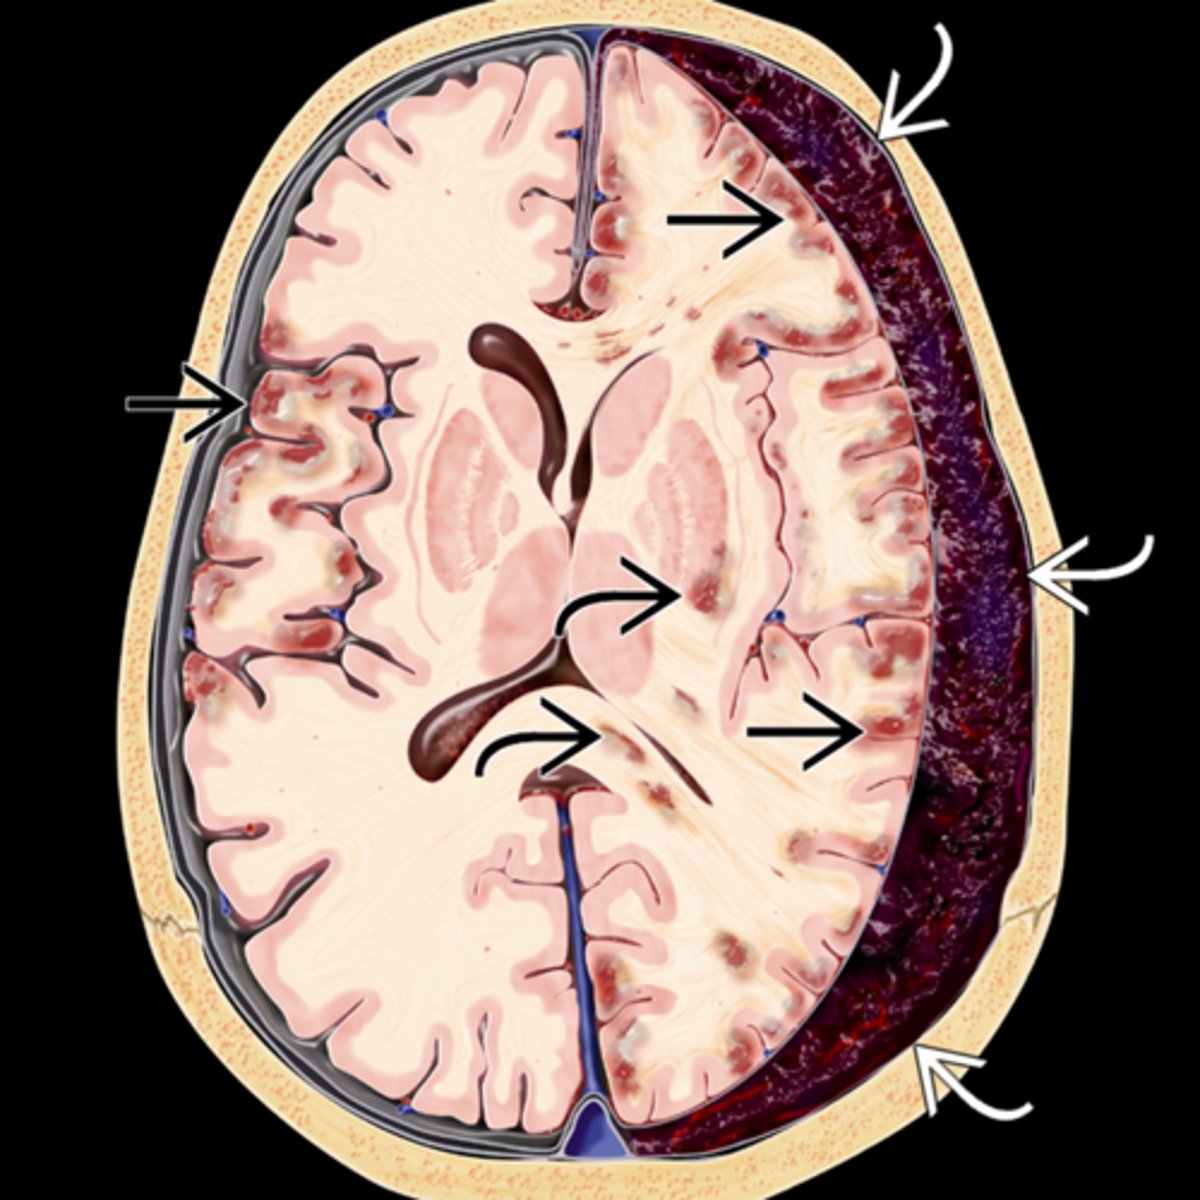

fast expanding mass, hemorrhage, tumor = increased ICP = brainstem compression and herniation down into foramen magnum (fatal!) = fixed, dilated pupil

Explain the progression of the Hutchinson pupil seen in Uncal syndrome.

1. miotic pupil due to initial cerbreal edema

2. ipsilateral dilated pupil due to expanding mass on that side

3. bilateral fixed and dilated pupils eventually

What are 3 other ocular signs of Uncal syndrome?

bilateral papilledema bc of increased ICP (bilateral even if only 1 pupil involved)

homonymous hemianopsia bc posterior cerebral arteries are occluded by mass = calcarine cortex ischemia

EOM paralysis = diplopia but mostly very late in the disease

What is the most common cause of Uncal syndrome?

chronic subdural hematoma from head trauma esp in inebriated pt's

What are some less common causes of Uncal syndrome?

extradural hematoma from injury

subdural hematoma from drugs

Explain the series of a events that causes a subdural hematoma, Uncal syndrome, and eventually death.

trauma = brain moves ant to post = cerebral veins in subdural space rip = blood fills subdural space = fibrous dura and arachnoid mesothelium beneath create a sac around the cot = sac breaks = blood enters brain = pt is sick and dies